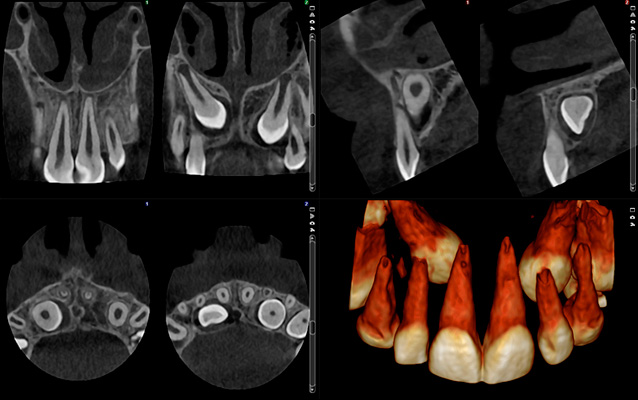

High resolutions and standard doses are not always necessary – often less is sufficient. Planmeca Ultra Low Dose 3D imaging is enough to see the mandibular nerve channel for implant planning and wisdom tooth extractions, for example. This can all be done at an incredibly low dose.

voxel size 150 μm, patient dose ~134 μSv

Very much detail, high dose

voxel size 150 μm, patient dose ~32 μSv

Much detail, low dose

voxel size 200 μm, patient dose ~86 μSv

Much detail, moderate dose

voxel size 200 μm, patient dose ~20 μSv

voxel size 400 μm, patient dose ~30 μSv

Less detail, low dose

voxel size 400 μm, patient dose ~6 μSv

Little detail, very low dose